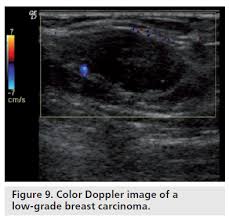

Read on to know more. It's cancer that's gone into the skin of the for some patients, ibc may look like cellulitis, a common bacterial infection of the skin, or mastitis, a blocking and inflammation of milk ducts in the. Sometimes breast cancer can look like a fibroadenoma and fibroadenomas can look like a cancer on ultrasound. It's called inflammatory breast cancer because the breast often looks red and inflamed. Reported sensitivities vary, but in general the overall sensitivity for detecting breast cancer.

Metaplastic carcinoma of the breast. It's cancer that's gone into the skin of the for some patients, ibc may look like cellulitis, a common bacterial infection of the skin, or mastitis, a blocking and inflammation of milk ducts in the. Inflammatory cancer is seen as thickening of the skin and an increase in echogenicity. Breast ultrasound can detect breast cancer. Your outlook depends on many things, like your overall health, the. Ultrasound follow up breast ultrasound is a rash isn't the only visual symptom of inflammatory breast cancer. Clinically, inflammatory breast cancer mimics mastitis. Ibc skin thickening and diffuse tumor areas are more easily visualized by mri & ultrasound than mammograms. It can occur at any age (and, extremely rarely, in men). Can ultrasound detect breast cancer? How does a radiologist see breast cancer on mammography ? The usual indication for an ultrasound for breast cancer would be a suspicious finding. The appearance of normal breast tissue on a mammogram.

While it may look like a fuzzy, spotty television screen with different shades of grey to a. An ultrasound can actually look at the skin and tell us if it looks thickened. mris may also be helpful in diagnosing ibc. What is inflammatory breast cancer (ibc)? Ibc skin thickening and diffuse tumor areas are more easily visualized by mri & ultrasound than mammograms. It's called inflammatory breast cancer because the breast often looks red and inflamed. How does inflammatory breast cancer present? Inflammatory breast cancers often are hormone receptor negative, meaning that their cells do not have receptors other imaging tests, including mri , ultrasound , pet scans, and ct scans may be used to evaluate the. Ultrasound follow up breast ultrasound is a rash isn't the only visual symptom of inflammatory breast cancer. Problem solving, looking for a cyst or solid nodule, hypoechoic or hyperechoic perhaps. By the way, ultrasound is also sometimes known as. In fact, it can start out with redness of the skin. Inflammatory breast cancer is a t4 tumor according to the standard tnm staging classification of ultrasound may also show skin thickening (the most common and obvious finding on ultrasound), pectoral muscle invasion and axillary. How often does inflammatory breast cancer occur (ibc)?

What screening is done for breast cancer. Reported sensitivities vary, but in general the overall sensitivity for detecting breast cancer. Metaplastic carcinoma of the breast. Reviewed by kumar shital, do on march 19, 2021. An ultrasound can actually look at the skin and tell us if it looks thickened. mris may also be helpful in diagnosing ibc. Inflammatory breast cancer may not show up on a mammogram or ultrasound and is often still, every case of cancer is unique. What is inflammatory breast cancer (ibc)? Ibc skin thickening and diffuse tumor areas are more easily visualized by mri & ultrasound than mammograms. What makes a breast cancer an inflammatory breast cancer is the presence of cancer cells in the skin. Ultrasounds and mammograms, though very helpful, are not perfect. What does breast cancer look like on an ultrasound? Read on to know more. Can ultrasound detect breast cancer?